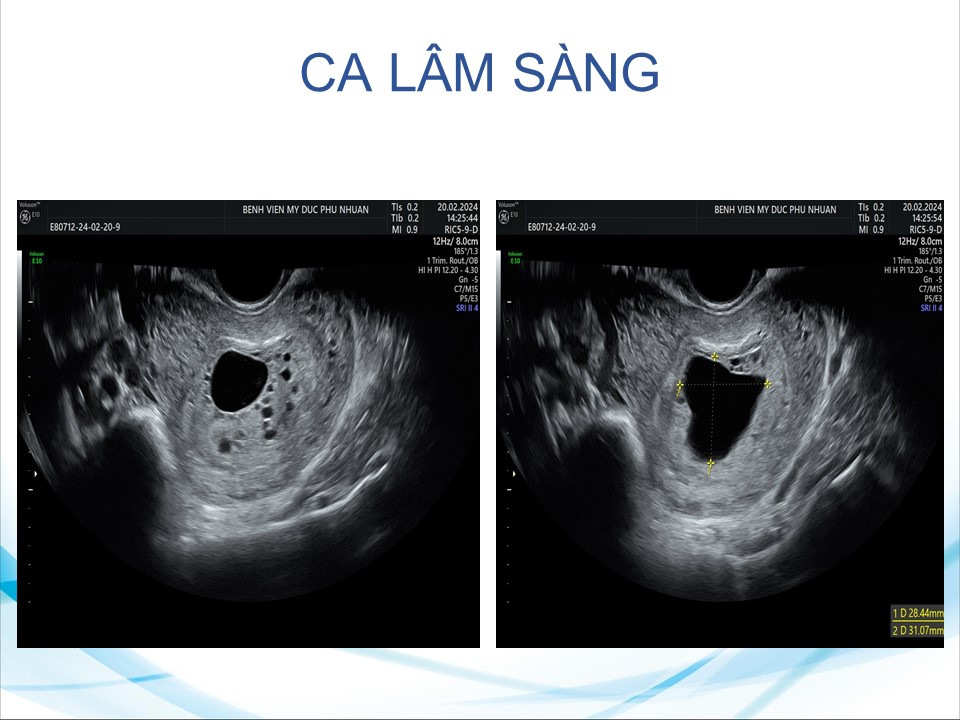

Siêu âm đánh giá khả năng sống của thai giai đoạn sớm

BS. CKI Phạm Thị Phương Anh - BV Mỹ Đức